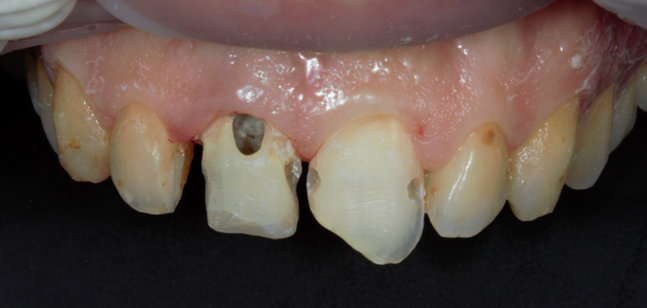

Εικόνα. Αφαίρεση όλων των παλαιών αποκαταστάσεων, αφαίρεση των τερηδονισμένων ιστών με σεβασμό στους οδοντικούς ιστούς χωρίς υπερβολική αφαίρεση αυτών.